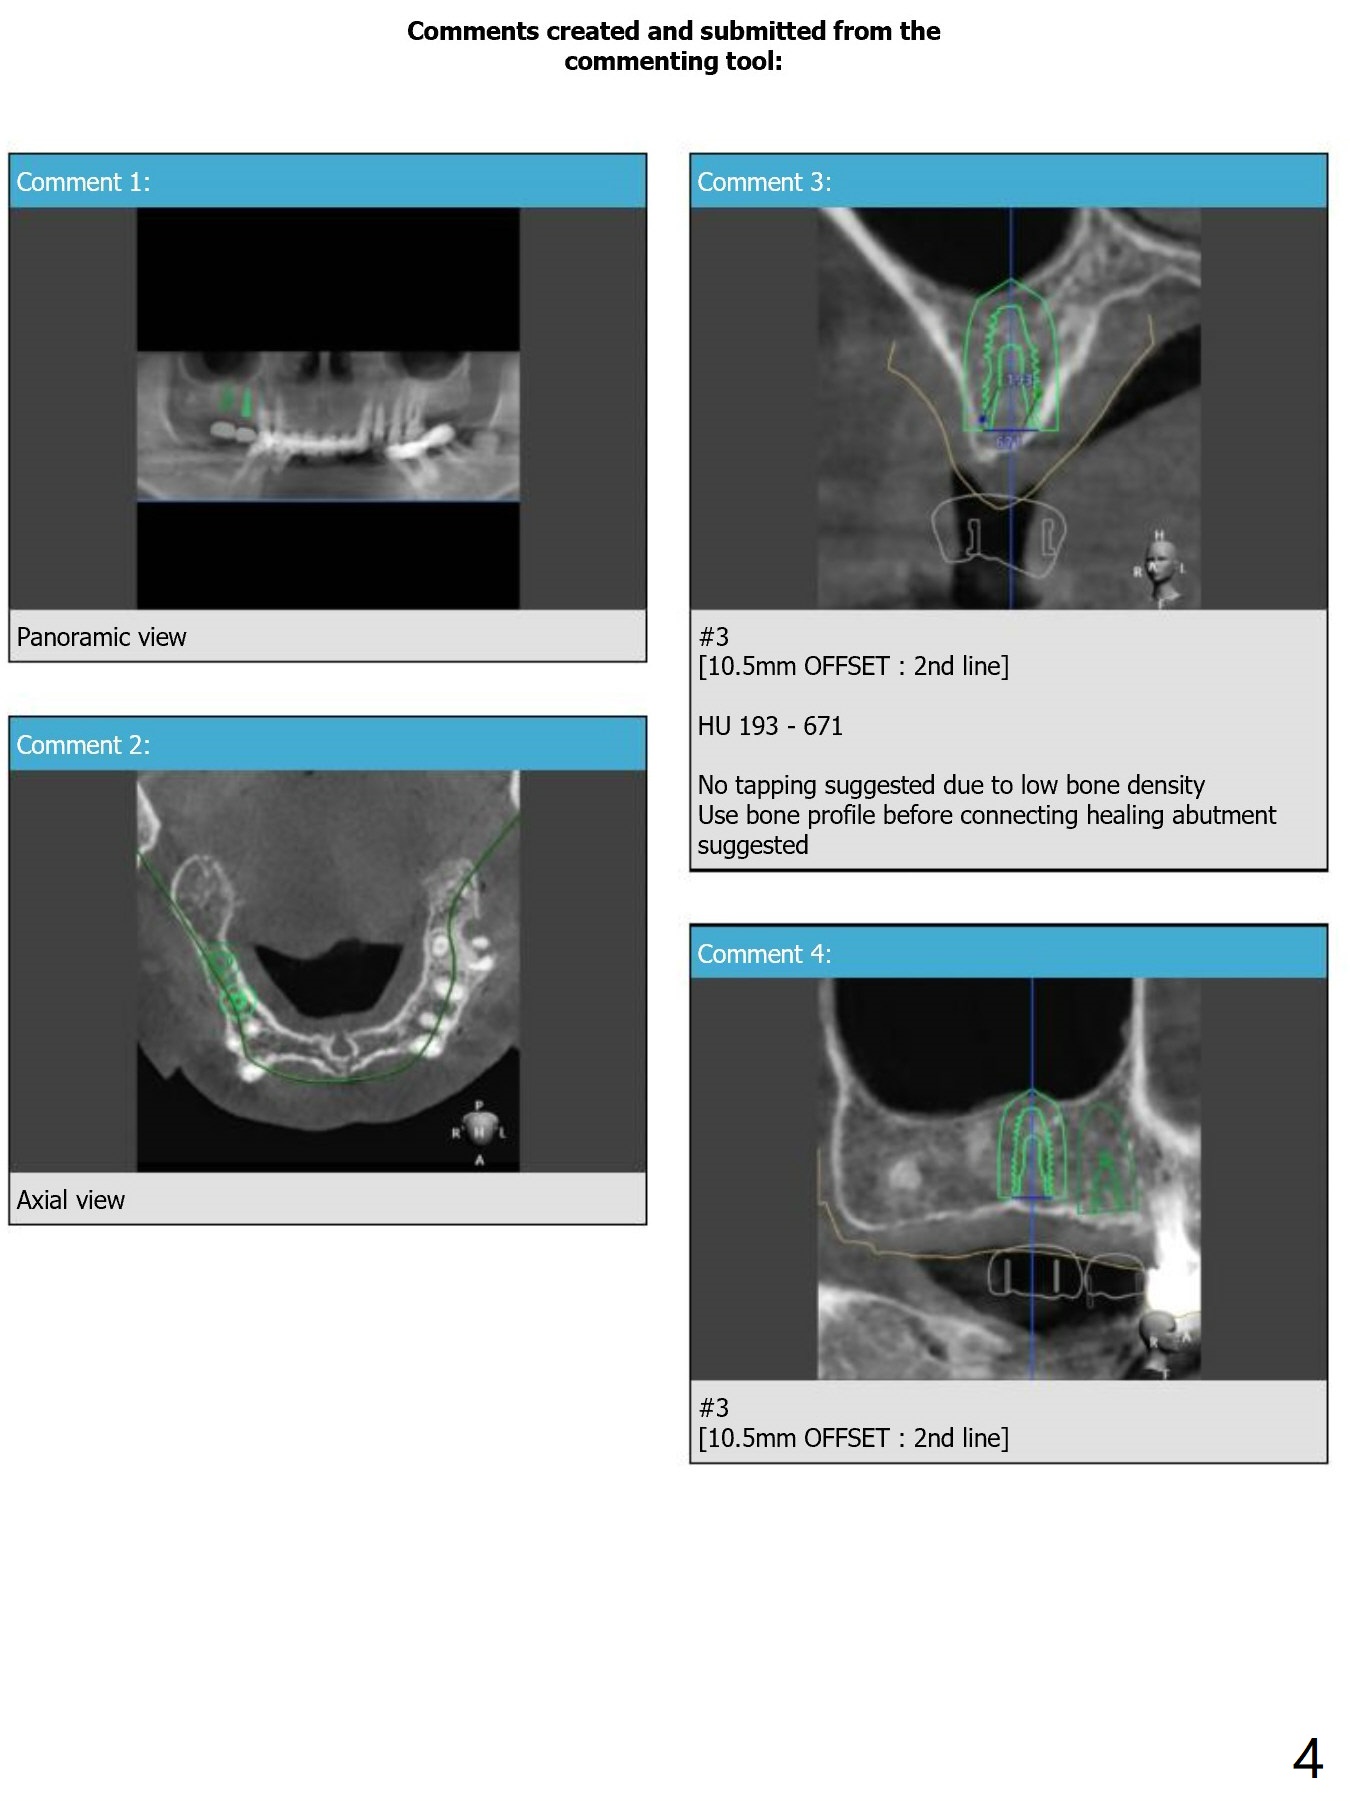

No Tap

Return to Upper Molar Premolar Immediate Implant, Trajectory